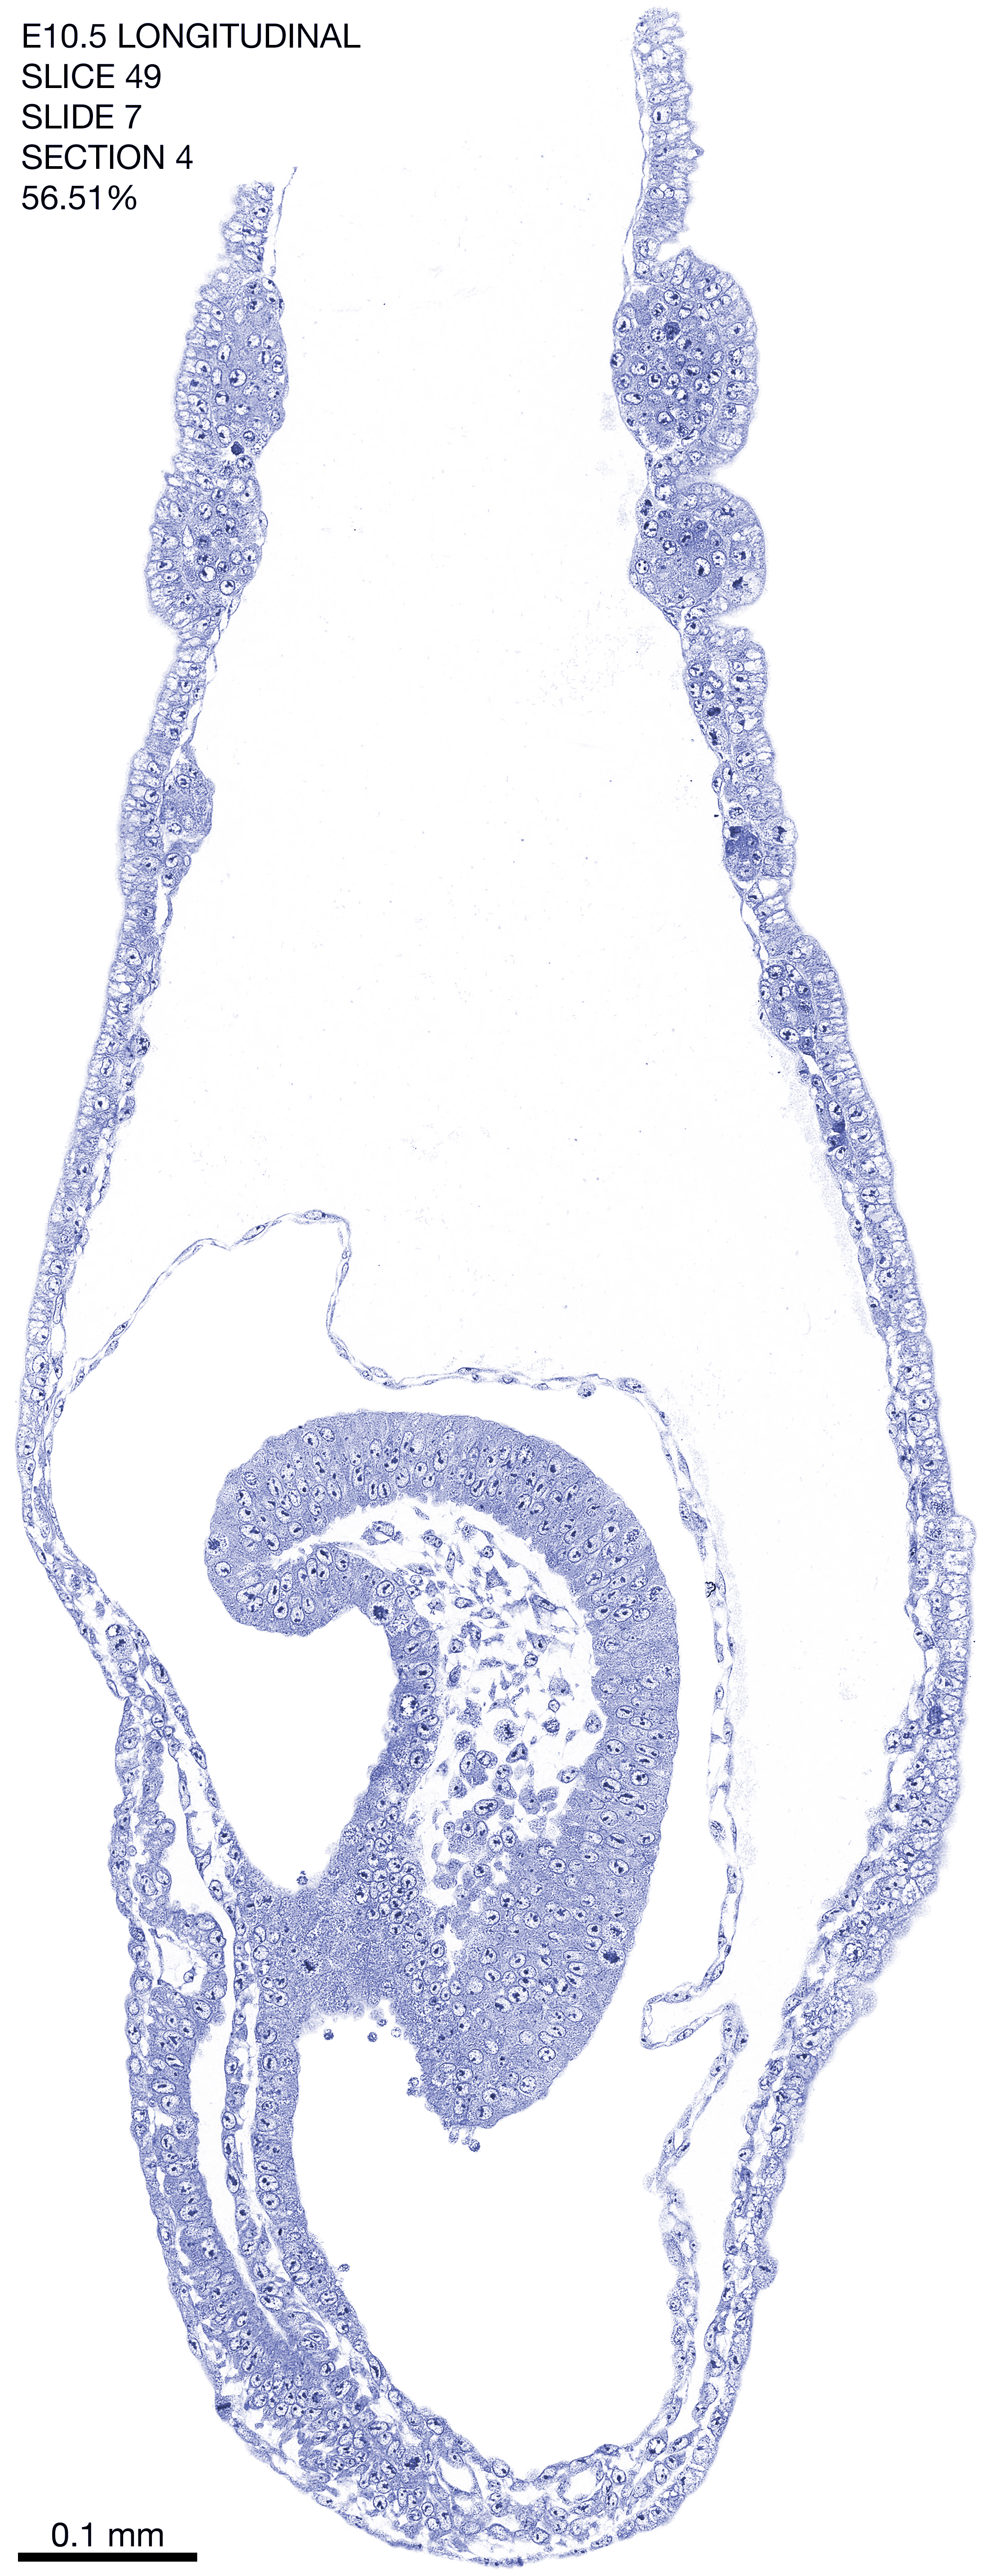

E10.5 Longitudianal Archive This page contains jpg files of ALL SLICES (each 3µm thick) that were scanned of the E10.5 longitudinally cut specimen. Download: Large | High Res Download: Large | High Res Download: Large | High Res Download: Large | High Res Download: Large | High Res Download: Large | High Res Download: Large | High Res Download: Large | High Res Download: Large | High Res Download: Large | High Res Download: Large | High Res Download: Large | High Res Download: Large | High Res Download: Large | High Res Download: Large | High Res Download: Large | High Res Download: Large | High Res Download: Large | High Res Download: Large | High Res Download: Large | High Res Download: Large | High Res Download: Large | High Res Download: Large | High Res Download: Large | High Res Download: Large | High Res Download: Large | High Res Download: Large | High Res Download: Large | High Res Download: Large | High Res Download: Large | High Res Download: Large | High Res Download: Large | High Res Download: Large | High Res Download: Large | High Res Download: Large | High Res Download: Large | High Res Download: Large | High Res Download: Large | High Res Download: Large | High Res Download: Large | High Res Download: Large | High Res Download: Large | High Res Download: Large | High Res Download: Large | High Res Download: Large | High Res Download: Large | High Res Download: Large | High Res Download: Large | High Res Download: Large | High Res Download: Large | High Res Download: Large | High Res Download: Large | High Res Download: Large | High Res Download: Large | High Res Download: Large | High Res Download: Large | High Res Download: Large | High Res Download: Large | High Res